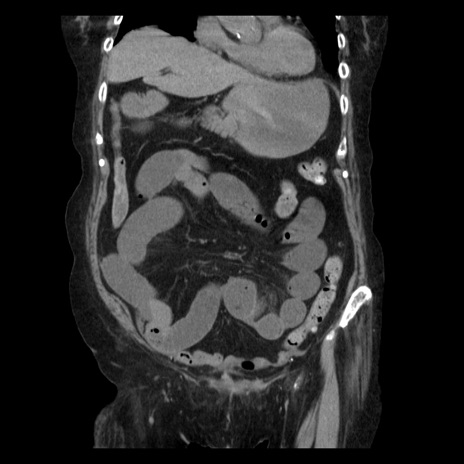

横断像

【症例】 90歳代女性

【主訴】 腹痛・嘔吐

【現病歴】今朝から左側腹部痛を認めた。 経過観察していたが、嘔吐を認めたため来院。

【既往歴】 子宮癌術後

【身体所見】 意識清明、BP 127/54mmHg、P 98bpm Sp02 95%(RA)、BT 35.8°C、腹部平坦・軟腸ぜん動音聴取良好、右下腹部圧痛(+) 反跳痛なし

【データ】WBC 9800、CRP 0.46